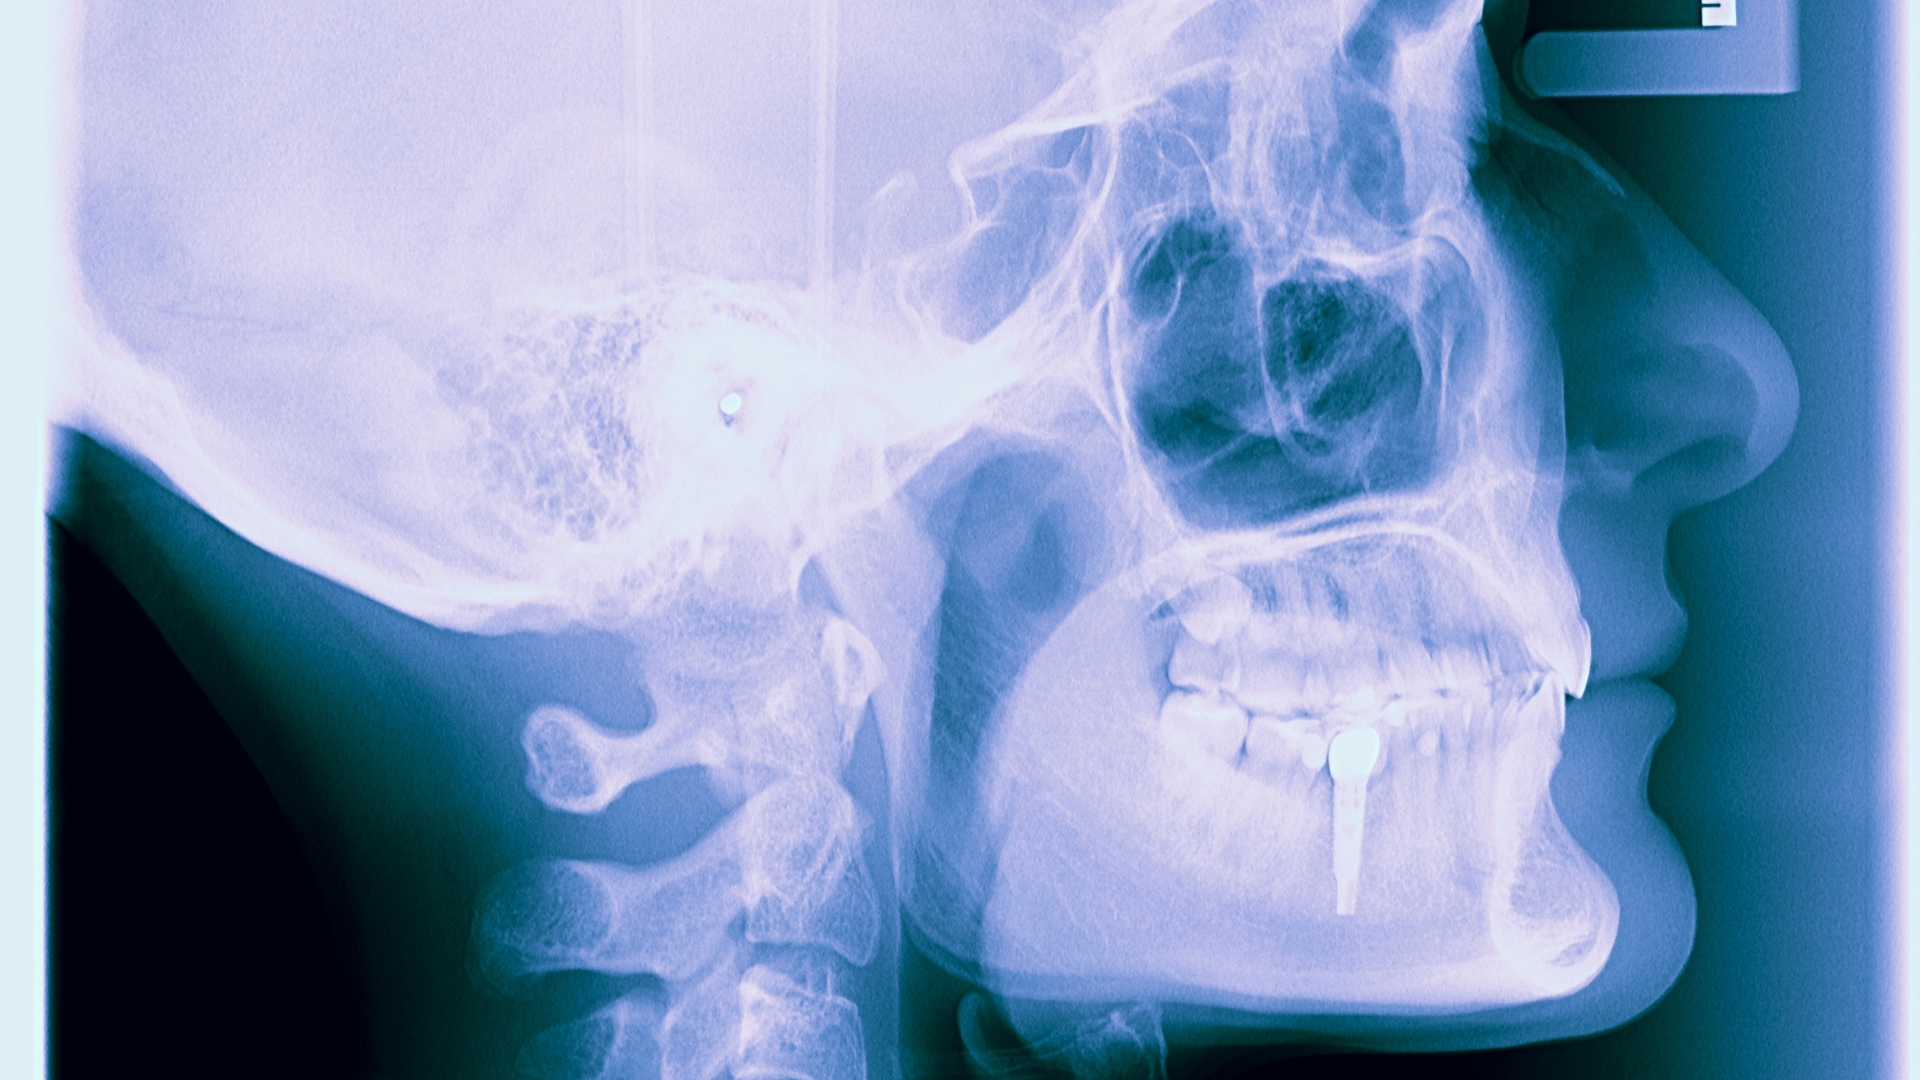

- Diagnosticar de manera precisa: Utilizamos tecnología avanzada como tomografías computarizadas 3D para evaluar la posición del implante y la salud del hueso circundante.